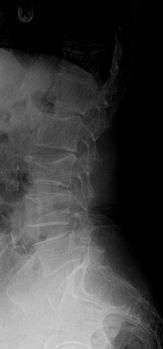

X-ray of the lumbar spine with a compression fracture of the third lumbar vertebra.